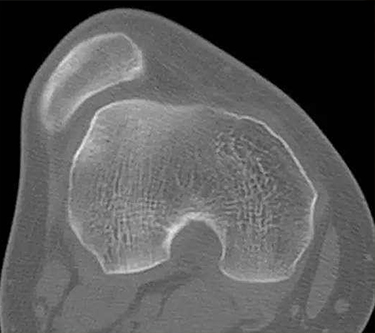

1、X线检查 针对习惯性髌骨脱位有很大的诊断价值。通常需拍膝关节的正侧位及髌骨轴位X线片,以显示髌骨的形态和位置是否正常。2、CT检查 可以更为准确的反映髌股关节情况。3、关节镜 其检查优势在于评估髌股关节软骨损害的程度,根据软骨损伤的程度决定手术方式。

根据临床表现和体征,结合X线、CT与关节镜检查通常均可明确诊断。